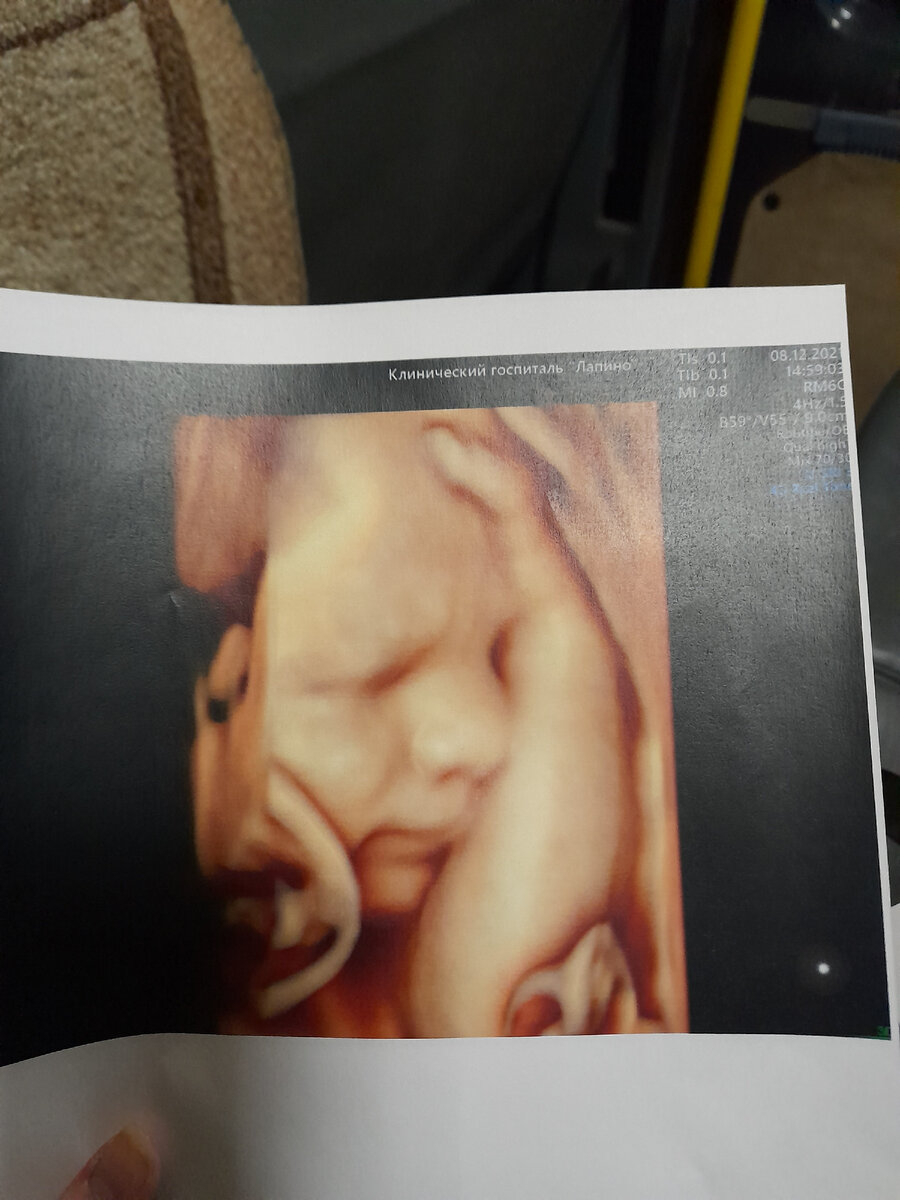

Я съездила им очень понравилась голова, что все осталось без изменений с октября месяца ,и это просто замечательно. Показали моего мальчишку( решили назвать его Юрой) ,даже фотографии дали. Дальше мне сказали, что рожать возможно я смогу сама ,но это решиться чуть позже ,но это будет  в роддоме 3  ,потом малыша переведут в больницу на Авиаторов,оперировать будет Асадов Когда я легла в роддом на следующий день мне провели кесарево сечение.  Показали нашего долгожданного малыша,также показали грыжу она была огромная. В этот же день его перевели в другую больницу. На следующий день ему провели операцию, она прошла успешно. Когда меня выписали из роддома я сразу поехала ложиться к Юре в больницу. Там нас смотрели много врачей ,но сказали что перспективы очень хорошие.  Двигательная активность сохранена. Выделительная система впорядке. Большое счастье что не подтвердились слова генетиков. Пока мы с Юрой лежали в патологии новорожденных и недоношенных детей я насмотрелась на детей с различ

Я съездила им очень понравилась голова, что все осталось без изменений с октября месяца ,и это просто замечательно. Показали моего мальчишку( решили назвать его Юрой) ,даже фотографии дали. Дальше мне сказали, что рожать возможно я смогу сама ,но это решиться чуть позже ,но это будет  в роддоме 3  ,потом малыша